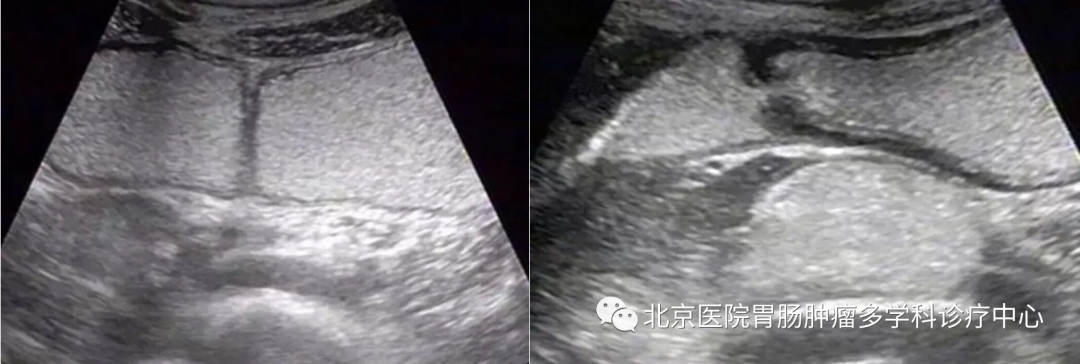

胃部超声及造影适用于儿童、孕妇、年迈体弱及患有慢性支气管炎等一系列对胃镜不耐受的患者。另外,对于一些慢性胃病患者,在接受第一个疗程的药物治疗后,临床医生可以通过胃部超声及造影观察胃肠功能的恢复情况,对下一个疗程进行评估。胃肠超声还可以对胃部肿瘤进行分级,观察肿瘤侵犯到胃壁的具体层次及周围淋巴结的转移情况,为临床手术治疗进行评估和提供治疗方案。对于胃部手术后的病人,也可以通过胃超声造影来评估胃蠕动和吻合口情况。